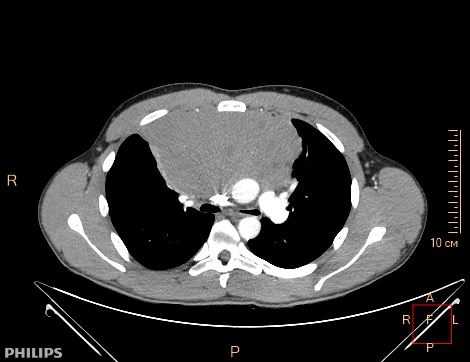

Рисунок 1а. Компьютерная томография пациента К, 31 лет с медиастинальным образованием (НМИЦ онкологии им. Н.Н. Петрова), аксиальная плоскость.

При поражении органов средостения рентгенологическая и клиническая картина неспецифичны (рис.1), только развернутый гистологический диагноз позволяет определиться с тактикой и подобрать эффективную терапию.

КТ ОГК. Объемное образование в средостении (патологически измененный лимфоузел), подтвержденная лимфома.